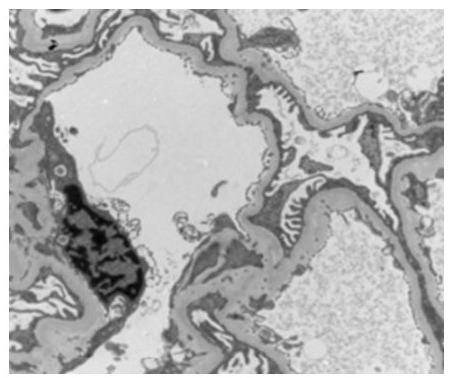

-A right renal biopsy was performed, yielding 10 glomeruli, a light microscopy revealed a segmental and focal glomerulosclerosis (FSGS) with no chronic lesions and no evidence of immune-mediated glomerulonephritis, morphological classification of FSGS (COLOMBIA): NOS (Figure 3).The electron microscopy showed podocyte foot process effacement typical lesion found inFSGS (Figure 4) and the immunofluorescence: IgA, IgG, IgM, C3, C1q was negative .

Figure 4: Electron microscopy study of kidney biopsy showed podocyte foot process effacement.

Recent discoveries have found that the PAX2 gene is re-expressed in nephropathy and acts as a suppressor of WT1, an important transcription factor of podocytes. Its mutation causes congenital nephrotic syndrome and FSGS [19]. In immune kidney diseases, Letavernier et al observed changes in podocyte phenotypes in focal segmental glomerulosclerosis (FSGS) and found that PAX2 is implicated in the pathogenesis of renal interstitial fibrosis and glomerulosclerosis [20]. Zhang et al found that in primary nephrotic syndrome, PAX2 expression in renal tubules in steroid-resistant children was significantly increased compared to steroid-sensitive children [21]. In 2014, PAX2 was found to be associated with adult-onset focal segmental glomerulosclerosis (FSGS) and was listed as a causative mutation of FSGS [22; 23]. In our case, the patient has proteinuria and FSGS in the kidney biopsy as shown in pictures 2-3. According to a recent Korean study, including 27 patients with PAX2 mutations detected from 2004–2022, 4 of them had FSGS [24].